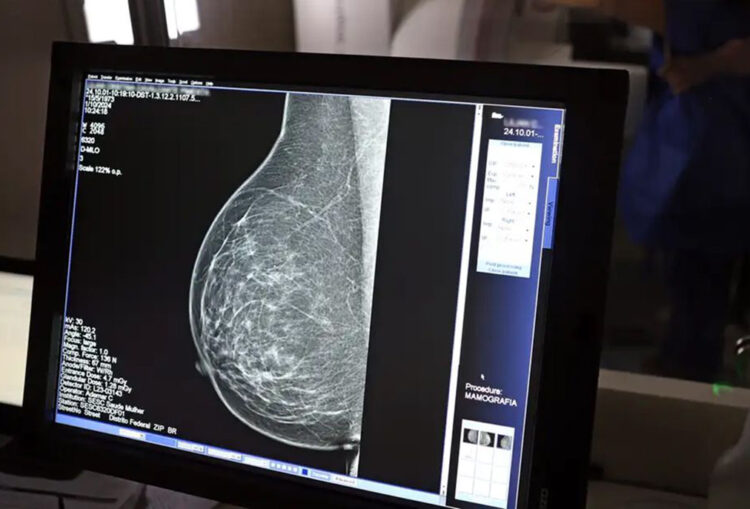

O objetivo é incentivar o autocuidado e ampliar o acesso aos exames preventivos de saúde feminina. Serão realizados cerca de 60 exames de mamografia e 50 de ultrassonografia por dia, totalizando mais de 100 atendimentos diários.

Os exames de ultrassonografia serão agendados previamente pela regulação municipal, que entrará em contato com pacientes já cadastrados na fila do SUS. Para a ultrassonografia mamária em mulheres acima de 40 anos, é obrigatório apresentar o laudo da última mamografia feita no período de um ano. Já os exames de mamografia terão demanda livre, sem necessidade de agendamento prévio.

Para ser atendido, o paciente deve apresentar documento oficial com foto, cartão do SUS e pedido médico original. Os resultados das ultrassonografias serão entregues no mesmo dia, enquanto os laudos das mamografias estarão disponíveis após dez dias na plataforma online da Secretaria Estadual de Saúde.